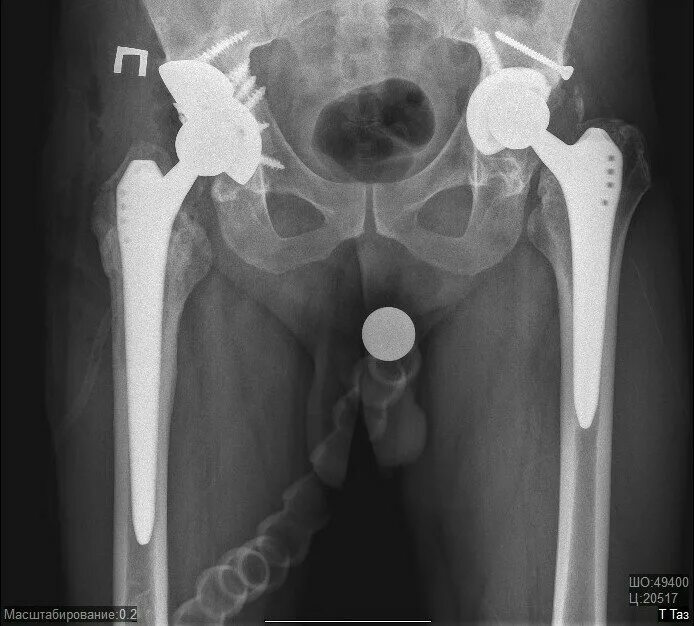

Ревизия тазобедренного сустава